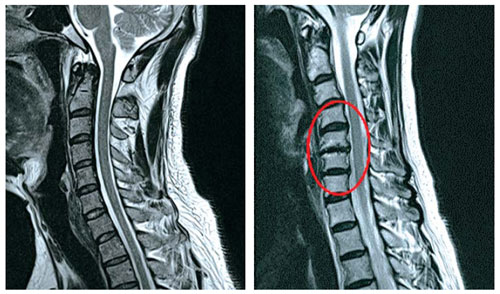

목 뼈와 뼈 사이의 디스크가 제자리에서 이탈되어 신경을 압박한 경우 혹은 뼈 조직이 비정상적으로 자라 목을 지나는 척추 신경이 눌려 통증을 인지하는 질환이예요.

디스크의 수핵이 빠져나가거나 퇴행성 경추 척추증 및 경추관협착증 등으로 척수가 눌리게 되면 대다수는 팔의 힘이 빠지는 느낌을 받을 수 있습니다.

목 디스크 증상으로 저림 현상을 겪으실 수 있어요. 이유는 디스크의 수핵이 빠져나가거나 퇴행성 경추 척추증등으로 척수가 눌리게 되므로 팔의 힘이 빠지고 저린 경우가 많기 때문에져요. 척수가 눌린 강도에 따라서는 팔이 마비가 되기도 하며, 어지럼증을 더불어 치를 수도 있어요.